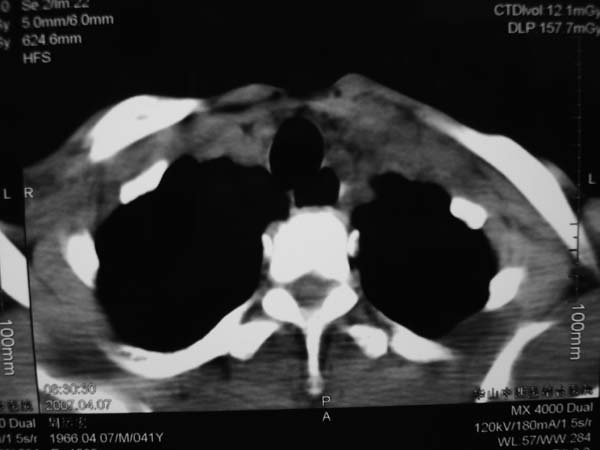

患者男性,37岁,农民,自觉左颈部肿大三天,无其它不适。

病灶边界较清,密度不均,其内可见坏死灶,左侧甲状腺受压,考虑神经源性肿瘤可能性大,建议穿刺活检。

病程短,症状轻,颈内动静脉显示不清,考虑血管病变。建议增强扫描。贸然穿刺可能会引起出血。

病灶边界较清,密度不均,其内可见坏死灶,左侧甲状腺受压,考虑神经源性肿瘤可能性大。